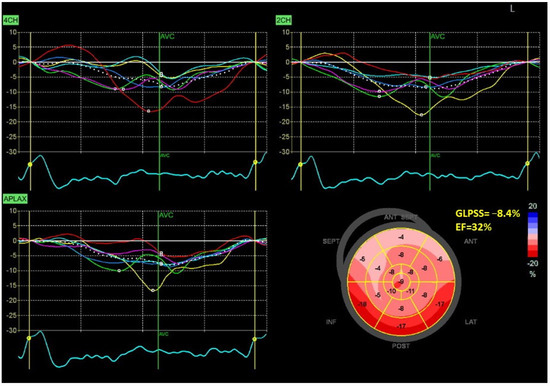

Figure 1 and Figure 2 show two contrasting examples (a healthy person and a patient after myocardial infarction and left bundle branch block) of STE curves with GLPSS, LVEF and LV pressure–strain loops and results of GWE for all LV segments.

Figure 2.

An example of echocardiography of a 61-year-old man with the left bundle branch block and a history of myocardial infarction. A set of individual longitudinal strain curves for all segments shown in different colors, with the average curve shown as a white dotted line, a bull’s eye of segmental longitudinal peak systolic strains and a summary of global longitudinal peak systolic strain (GLPSS) are shown in the top panel. The LV pressure–strain loop with the bull’s eye representation of myocardial work efficiency for each of the segments and a summary of all myocardial work indices are shown in the lower panel. Abbreviations: GLS—global longitudinal peak systolic strain, EF—ejection fraction, GWI—global myocardial work index, GCW—global constructive work, GWW—global wasted work, GWE—global work efficiency, BP—blood pressure.